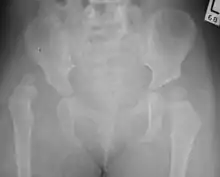

Hip dysplasia can be diagnosed by ultrasound[42] and projectional radiography ("X-ray").[43] Ultrasound imaging is generally preferred at up to 4 months due to limited ossification of the femoral head up until then, and is the most accurate method for imaging of the hip during the first few months after birth. However, in most instances, ultrasound screening should not be performed before 3 to 4 weeks of age because of the normal physiologic laxity.[44][notes 1] When universal with targeted ultrasound screening was compared, the former results in an insignificant reduction in the late diagnosis of hip dysplasia, which is why universal ultrasonographic screening of newborn infants is not recommended by the American Academy of Pediatrics.[11]

Despite the widespread use of ultrasound, pelvis X-ray is still frequently used to diagnose or monitor hip dysplasia or for assessing other congenital conditions or bone tumors.[45]

The most useful lines and angles that can be drawn in the pediatric pelvis assessing hip dysplasia are as follows:[45] Different measurements are used in adults.[45]